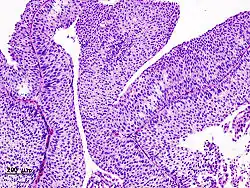

The 1973 WHO grading system for transitional cell carcinomas (papilloma, G1, G2 or G3) is most commonly used despite being superseded by the 2004 WHO[14] grading for papillary types (papillary neoplasm of low malignant potential [PNLMP], low grade, and high grade papillary carcinoma). High-grade carcinoma typically displays more pleomorphism, multiple mitoses, euchromatin and relatively prominent nucleoli, and uneven distribution of nuclei.

Transitional cell carcinoma, being low-grade to the left, and high-grade to the right. H&E stain -

Histopathology of urothelial carcinoma of the urinary bladder, showing a nested pattern of invasion. Transurethral biopsy. H&E stain -